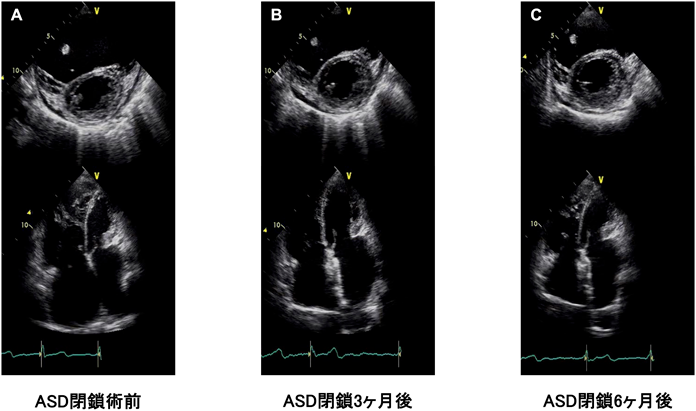

ただ,高齢者では左室拡張障害を伴うことがあり,ASD閉鎖術で左室容量負荷が増え,左房圧が上昇し,肺うっ血が出現することが危惧される6, 7).最近では,左室駆出率の保持された心不全症例では,肺うっ血軽減のため心房間シャントを作成するデバイスも存在する8).また,左室拡張障害を伴った症例での経カテーテルASD閉鎖術でも術前に利尿薬を使用して慎重に体液コントロールを行い,時には強心薬等の静注薬を併用することで,安全にASD閉鎖術を行うことが可能である(Fig. 26, 9)

Fig. 2 高齢者のASDに対する経カテーテル閉鎖術前後での心エコーの変化

(A)80歳代の未治療ASDの症例.ASD閉鎖術前では右心系は高度に拡大し,左室は右室に圧排されていた.(B)経カテーテルASD閉鎖術3か月では,右心系の拡大や左心系の圧排もやや改善していた.(C)経カテーテルASD閉鎖術6か月では,さらに右心系のサイズは縮小し左室の圧排所見も改善していた.ASD=atrial septal defect